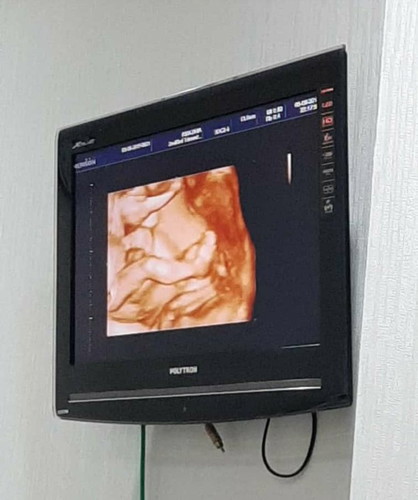

Masyallah tabarakallah, seneng itu liat perkembangan bayi kita ya bun. Apalagi sy hamil kembar. Say cek up di RS Dhia ciputat tangeranh. Spog saya laki2, namanya Dr. Mufti. Beliau super enak. Ditanya apa aja dijawab, dikasih tau ini itu.. Bahkan sejak kehamilan umur 4bulan, saya dikasih liat debay2 saya secara 4D. Tp di kasir ttp tagihan 2D hihi. Baik bgd lah. Kmrn cek up 20w alhamdulillah kembar sehat.. Buat bunda2 yg daerah ciputat tangerang, boleh dicoba cek up disana. Tp disana g ada BPJS ya. Dan jgn terlalu kepikiran dgn dokter cowo ini itu, dokter insyallah profesional. G perlu malu dll. Bahkan menurutku lbh enak dokter cowo karna lbh santai ? Cocok2an sih ya.. Happy pregnant mom ??

Senengnya alhamdulillah punya dede kembar si bunda.... Sehat sehat ya bunda dan si kembarnya lg musim hamil kembar sptnya y bund πππβ’ Sama bgt bund... Hehe aku di rs hermina bekasi juga gitu usg 4 d tp bayarnya 2 d.... Spognya juga alhamdulillah recomend dr. Yuditya Purwosunu spog(k) ...beliau ahli fetomaternal bgt... Review di google trnyta juga bnyk hihihi... Semangat bunda....